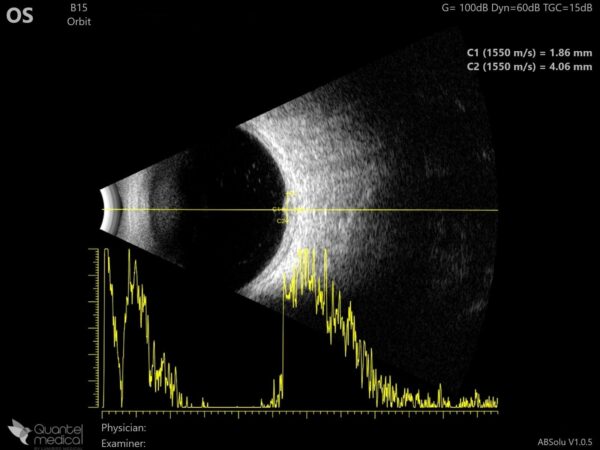

B-scan ultrasonography displayed a thin band of moderate reflectivity at the lesion site in the posterior pole, without acoustic hollowness (Figure 6).

Figure 6: B-mode ultrasonogram (Quantel Medical ABSolu®) of the left eye showing relatively high and homogeneous reflectivity of the posterior pole lesion.